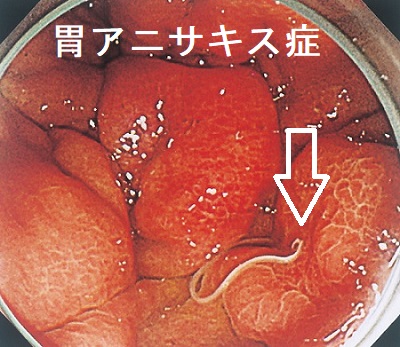

アニサキス症

胃・腸管アニサキス症には、

- 強烈な腹痛・嘔吐の劇症型

- 発疹や痒みの軽症型

があります。腸管外アニサキス症ではアニサキス抗体IgG・IgA検査が有用。

胃・腸管アニサキス症の予防は、

- 生の魚は一度、冷凍する

- 冷凍していたか不明な場合は、よく噛んで虫体を殺虫する

小腸アニサキス症

腹部CT検査で腸管浮腫、腸閉塞を認めれば見当つきます。顔面、体感のアニサキスアレルギーを疑う発疹も参考になります。確定診断は、小腸カプセル内視鏡ですが、もし見つけてもカメラは届かないのでアニサキスを捕れません。

軽症例は7日程度でアニサキス虫体の死亡により改善するので対症療法で良いですが、重症例は開腹手術になります。

(造影CT画像 岡山医学会雑誌(2009)121, 25-27)